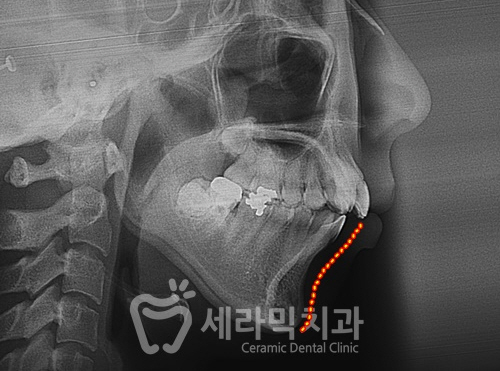

측면에서 보면 위쪽 앞니 돌출이 확연하게 확인됩니다.

윗니의 돌출에 비해서는 정도가 심하지 않아 보이지만,

아랫니도 상당한 경사를 이루면서 앞으로 기울어져 있습니다.

④ 무턱

사례자분을 옆에서 볼 때 턱선이 구분되지 않거나

심하게 입이 튀어나와 보이시진 않았습니다.

이 사진만 보면 무턱이 맞나 싶은 생각이 들 수도 있습니다.

하지만, 정면 사진을 보면

코끝에서 입술까지의 길이와 입술에서 턱끝까지의 길이가

큰 차이가 없어보이는 걸 확인하실 수 있습니다.

(정면에서 볼 때 코끝입술 : 입술턱끝은 1:2의 비율을 이상적인 비율로 보고 있습니다.)

정면에서 웃는 얼굴을 보면 아래턱이 더 뒤로 들어가면서 짧아보입니다.

정리를 하면,

아래턱이 위턱에 비해 작으면서 뒤로 들어가 있기 때문에,

측면보다 정면에서 볼 때 더욱 아래턱이 작아보이는 경우입니다.

치아교정으로 실제 아래 턱뼈를 더 길어지게 하는 것은 아닙니다.

많이 기울어진 채, 뒤로 들어가 있던 아래 턱뼈를

치아교정을 통해 곧게 세우면서 앞으로 나오게 만들어,

특히 정면 인상에서는 턱뼈가 길어진 것처럼 보이게 된 것입니다.

[아래 치아와 잇몸뼈의 변화]